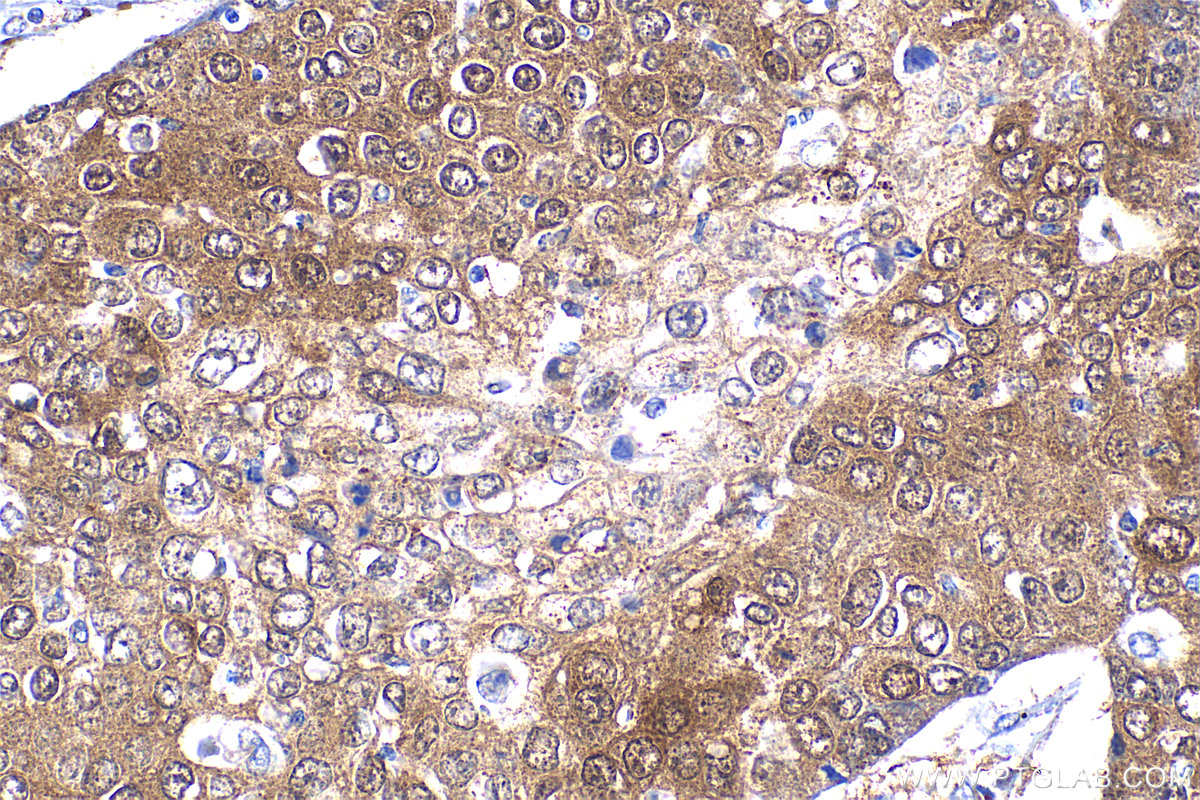

| Positive IHC detected in | human tonsillitis tissue, human lung cancer tissue Note: suggested antigen retrieval with TE buffer pH 9.0; (*) Alternatively, antigen retrieval may be performed with citrate buffer pH 6.0 |

| Immunohistochemistry (IHC) | IHC : 1:50-1:500 |